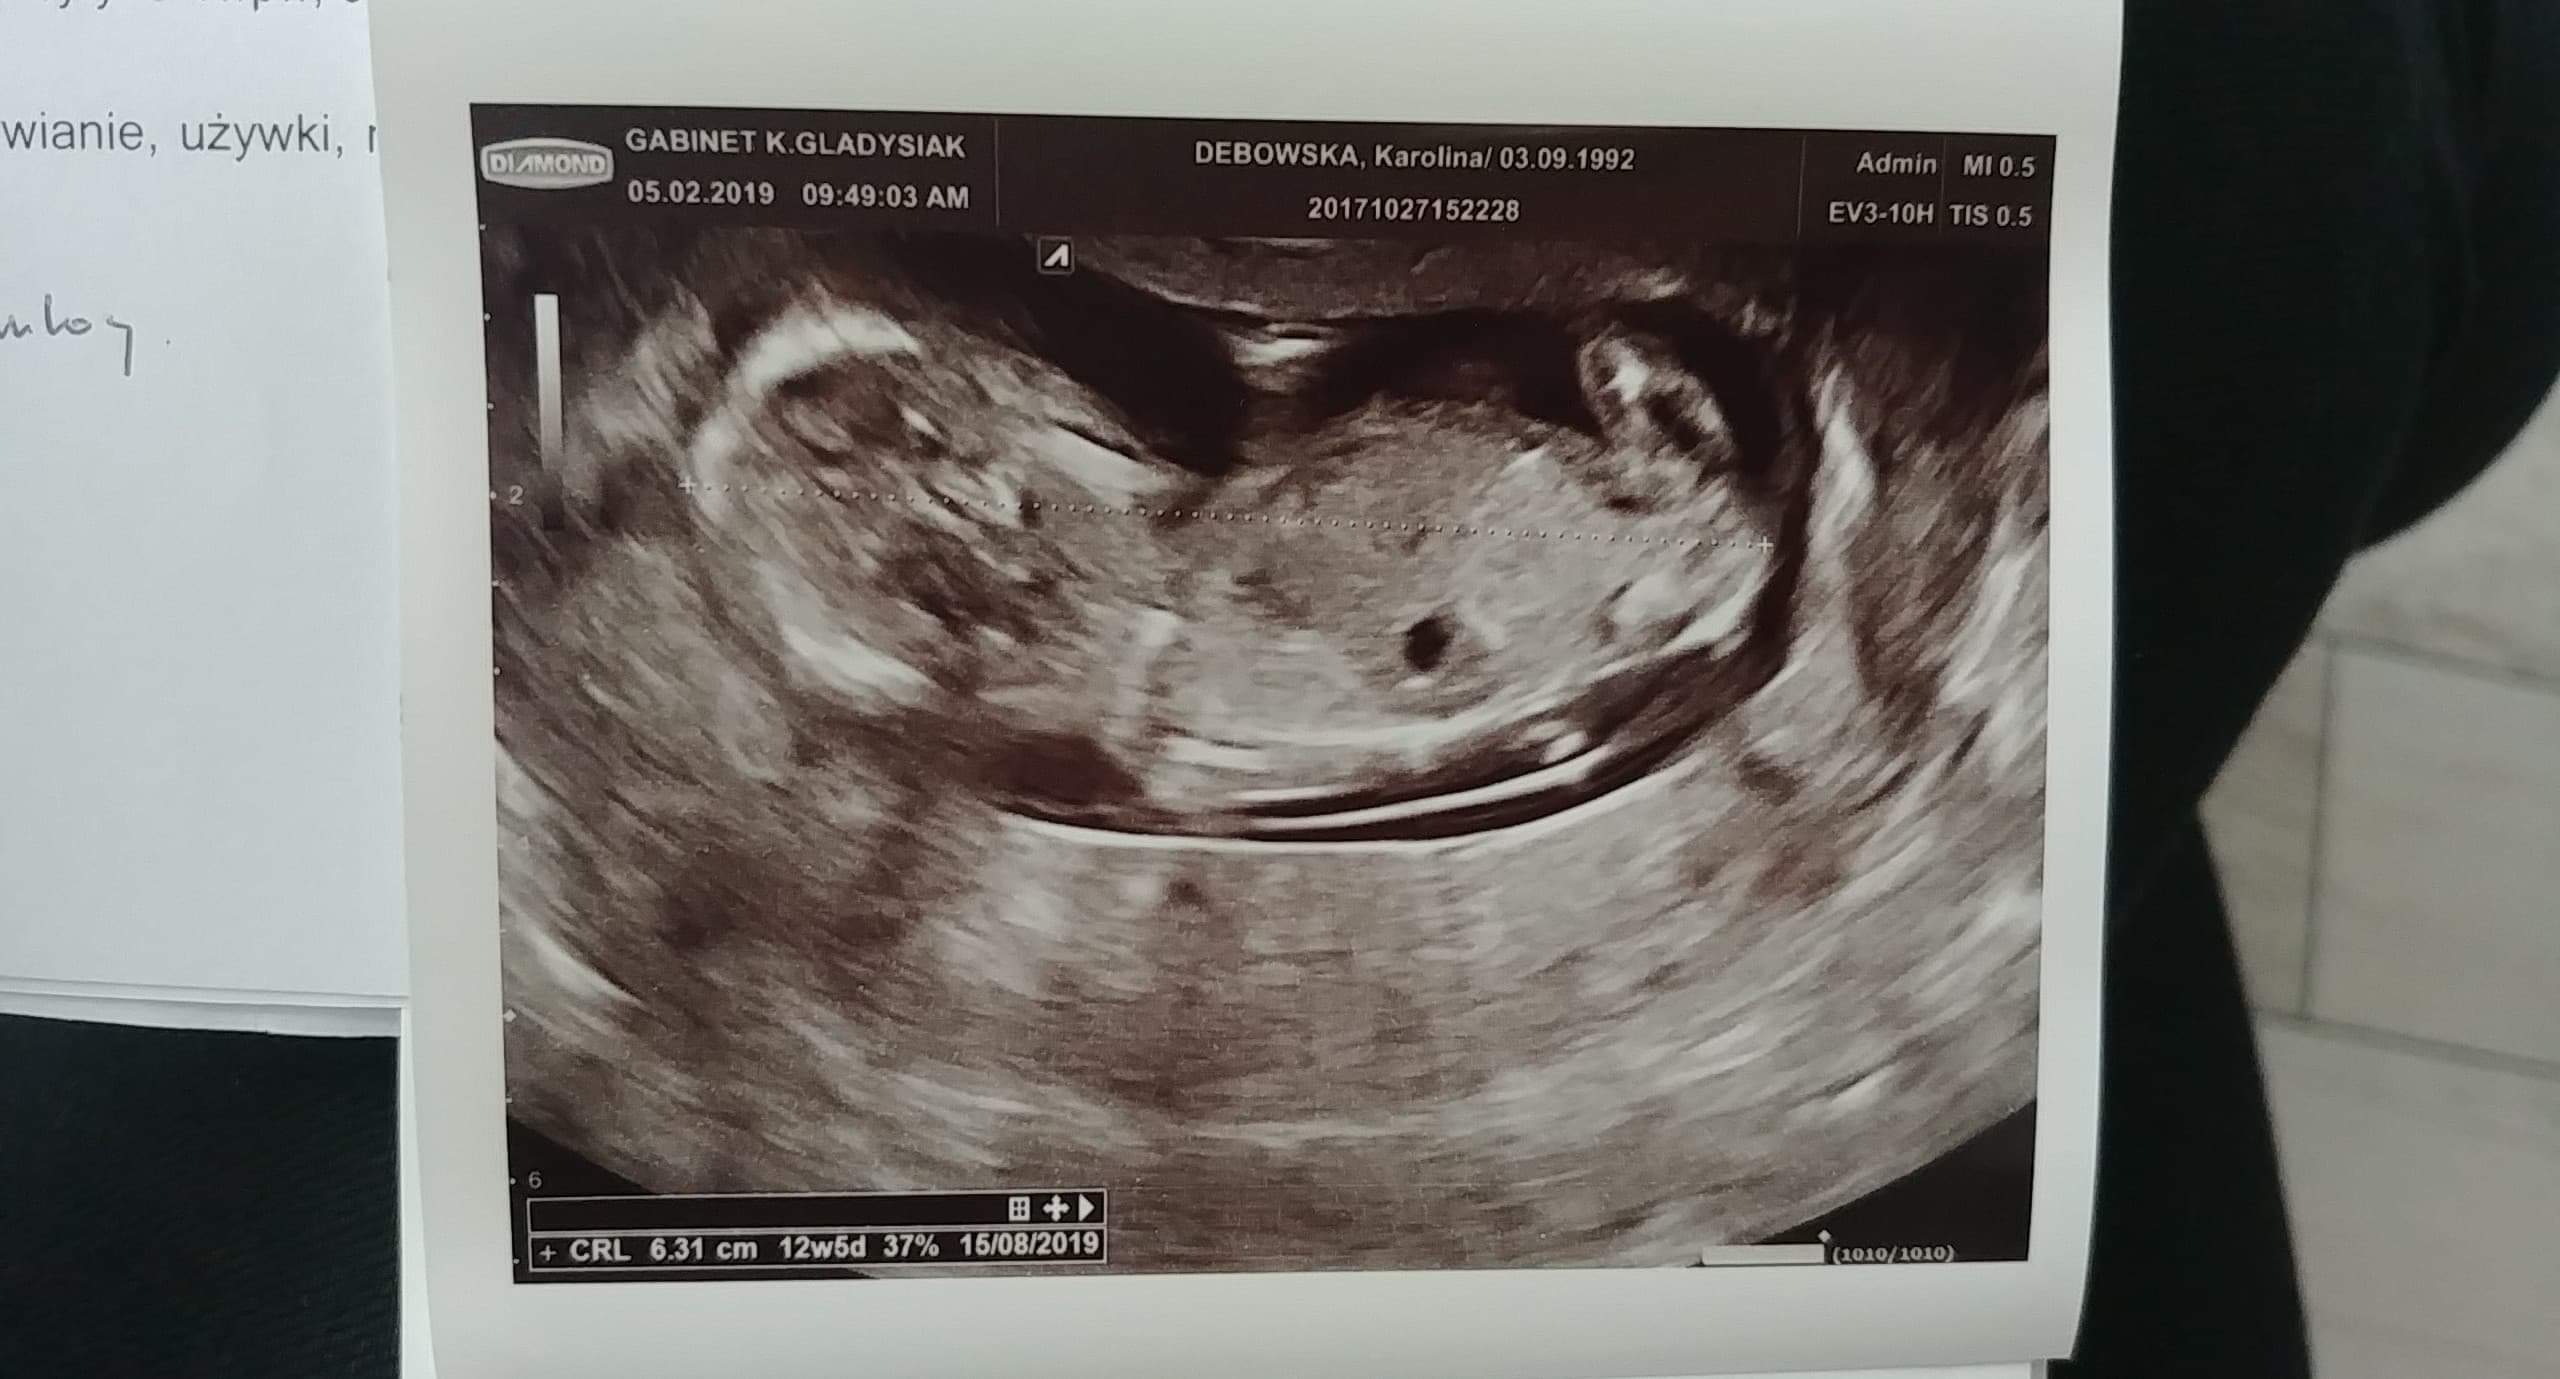

Hej, dziewczyny byłam ma prenatalnych i lekarz powiedzial ze na 90 % chlopak,później bylam u swojego gin i ze tez chlopak. Wczoraj bylam i juz mowi ze dziewczynka.. Mam tylko dwa zdjęcia niestety.

Załączniki

• received_255891791983613.jpeg

received_255891791983613.jpeg

191,7 KB · Wyświetleń: 562

• 20190305_093755.jpg

20190305_093755.jpg

1,1 MB · Wyświetleń: 555